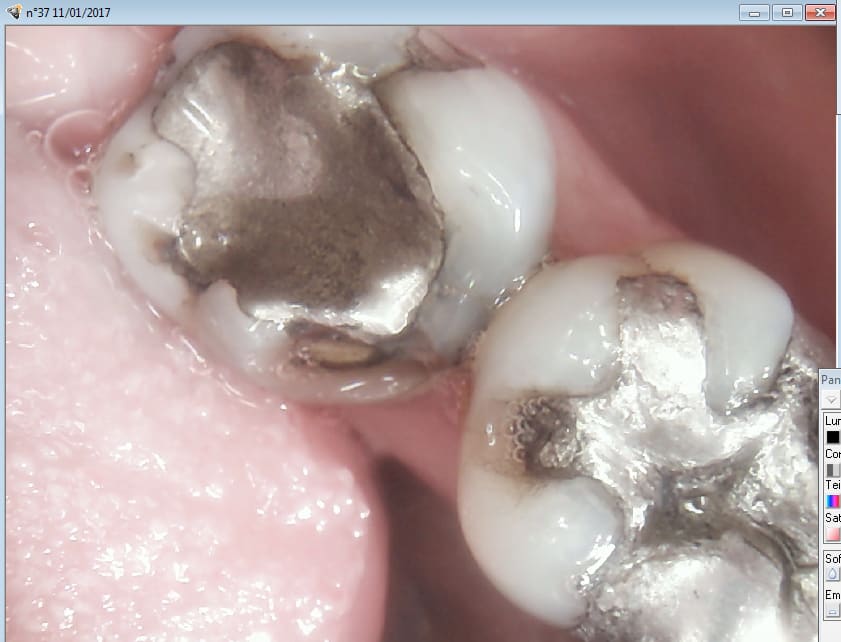

> , je ne comprends toujours pas pourquoi cette 15 te faisait peur et pourquoi

> avoir privilégié une 37 qui , au vu de la radio ne me pose pas plus de pb que ça

Ben voyons. Elle est intacte. -))))

Vous faites quoi là dessus ??

1 Vous attendez.

2 vous refaites un amalgame ou un composite.

3 Un onlay.

4 couronne sur dent vivante.

5 endo SC33

6 endo sc 33 coiffe.

7 endo ic coiffe.

Toutes les options sont défendables sauf les 2 premières ca va péter. -)

mais sur cette 37 y avait une carie ? Le plombage était cassé au point qu'il fallait couronner et dépulper ? Ou le plombage était trop volumineux peut être ?

Casa si tu regardes bien En L de 37 c'est cassé... donc onlay au minimum sur 37 pulpée ou couronne sur 37 à dépulper en fonction de ce qu'on découvre